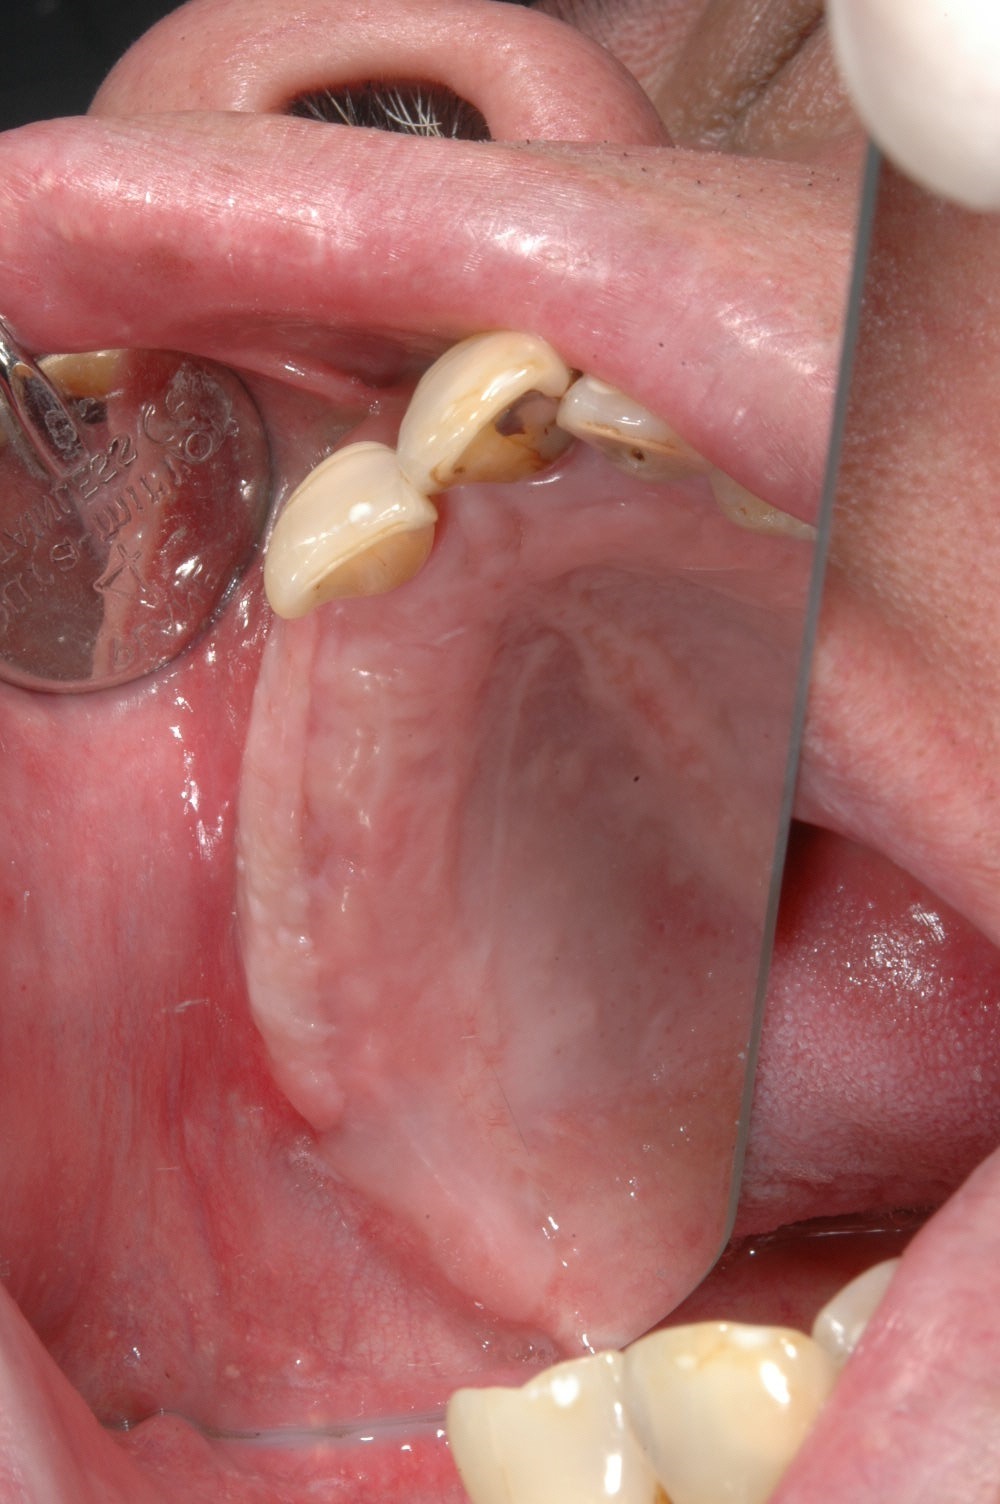

牙齦移植術(補肉)

利用自體牙齦組織移植至牙齦萎縮處或是角質化牙齦不足的地方,恢復牙齦美觀與健康,以利未來植牙提供穩定的牙周環境。